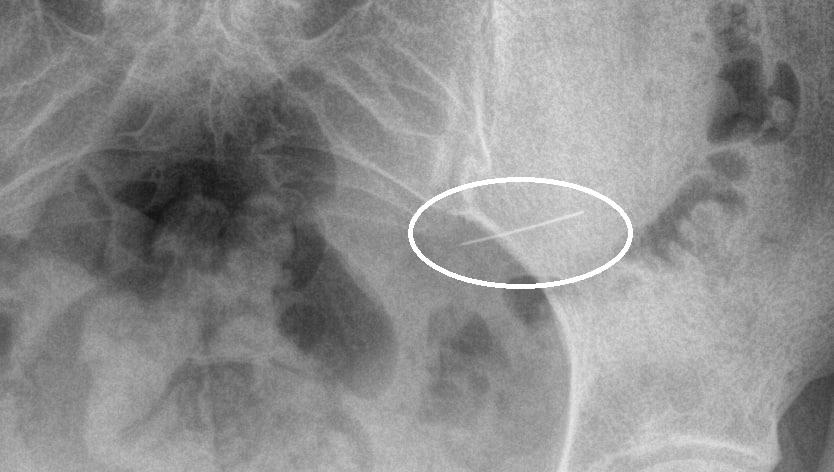

В больнице пациентке сделали рентгенологическое исследование, которое показало: инородное тело пока еще находится в желудке.

По словам Николая Мурашова, заведующего первым хирургическим отделением стационара, врачам удалось благополучно извлечь опасный предмет — без разрезов, с помощью эндоскопии.